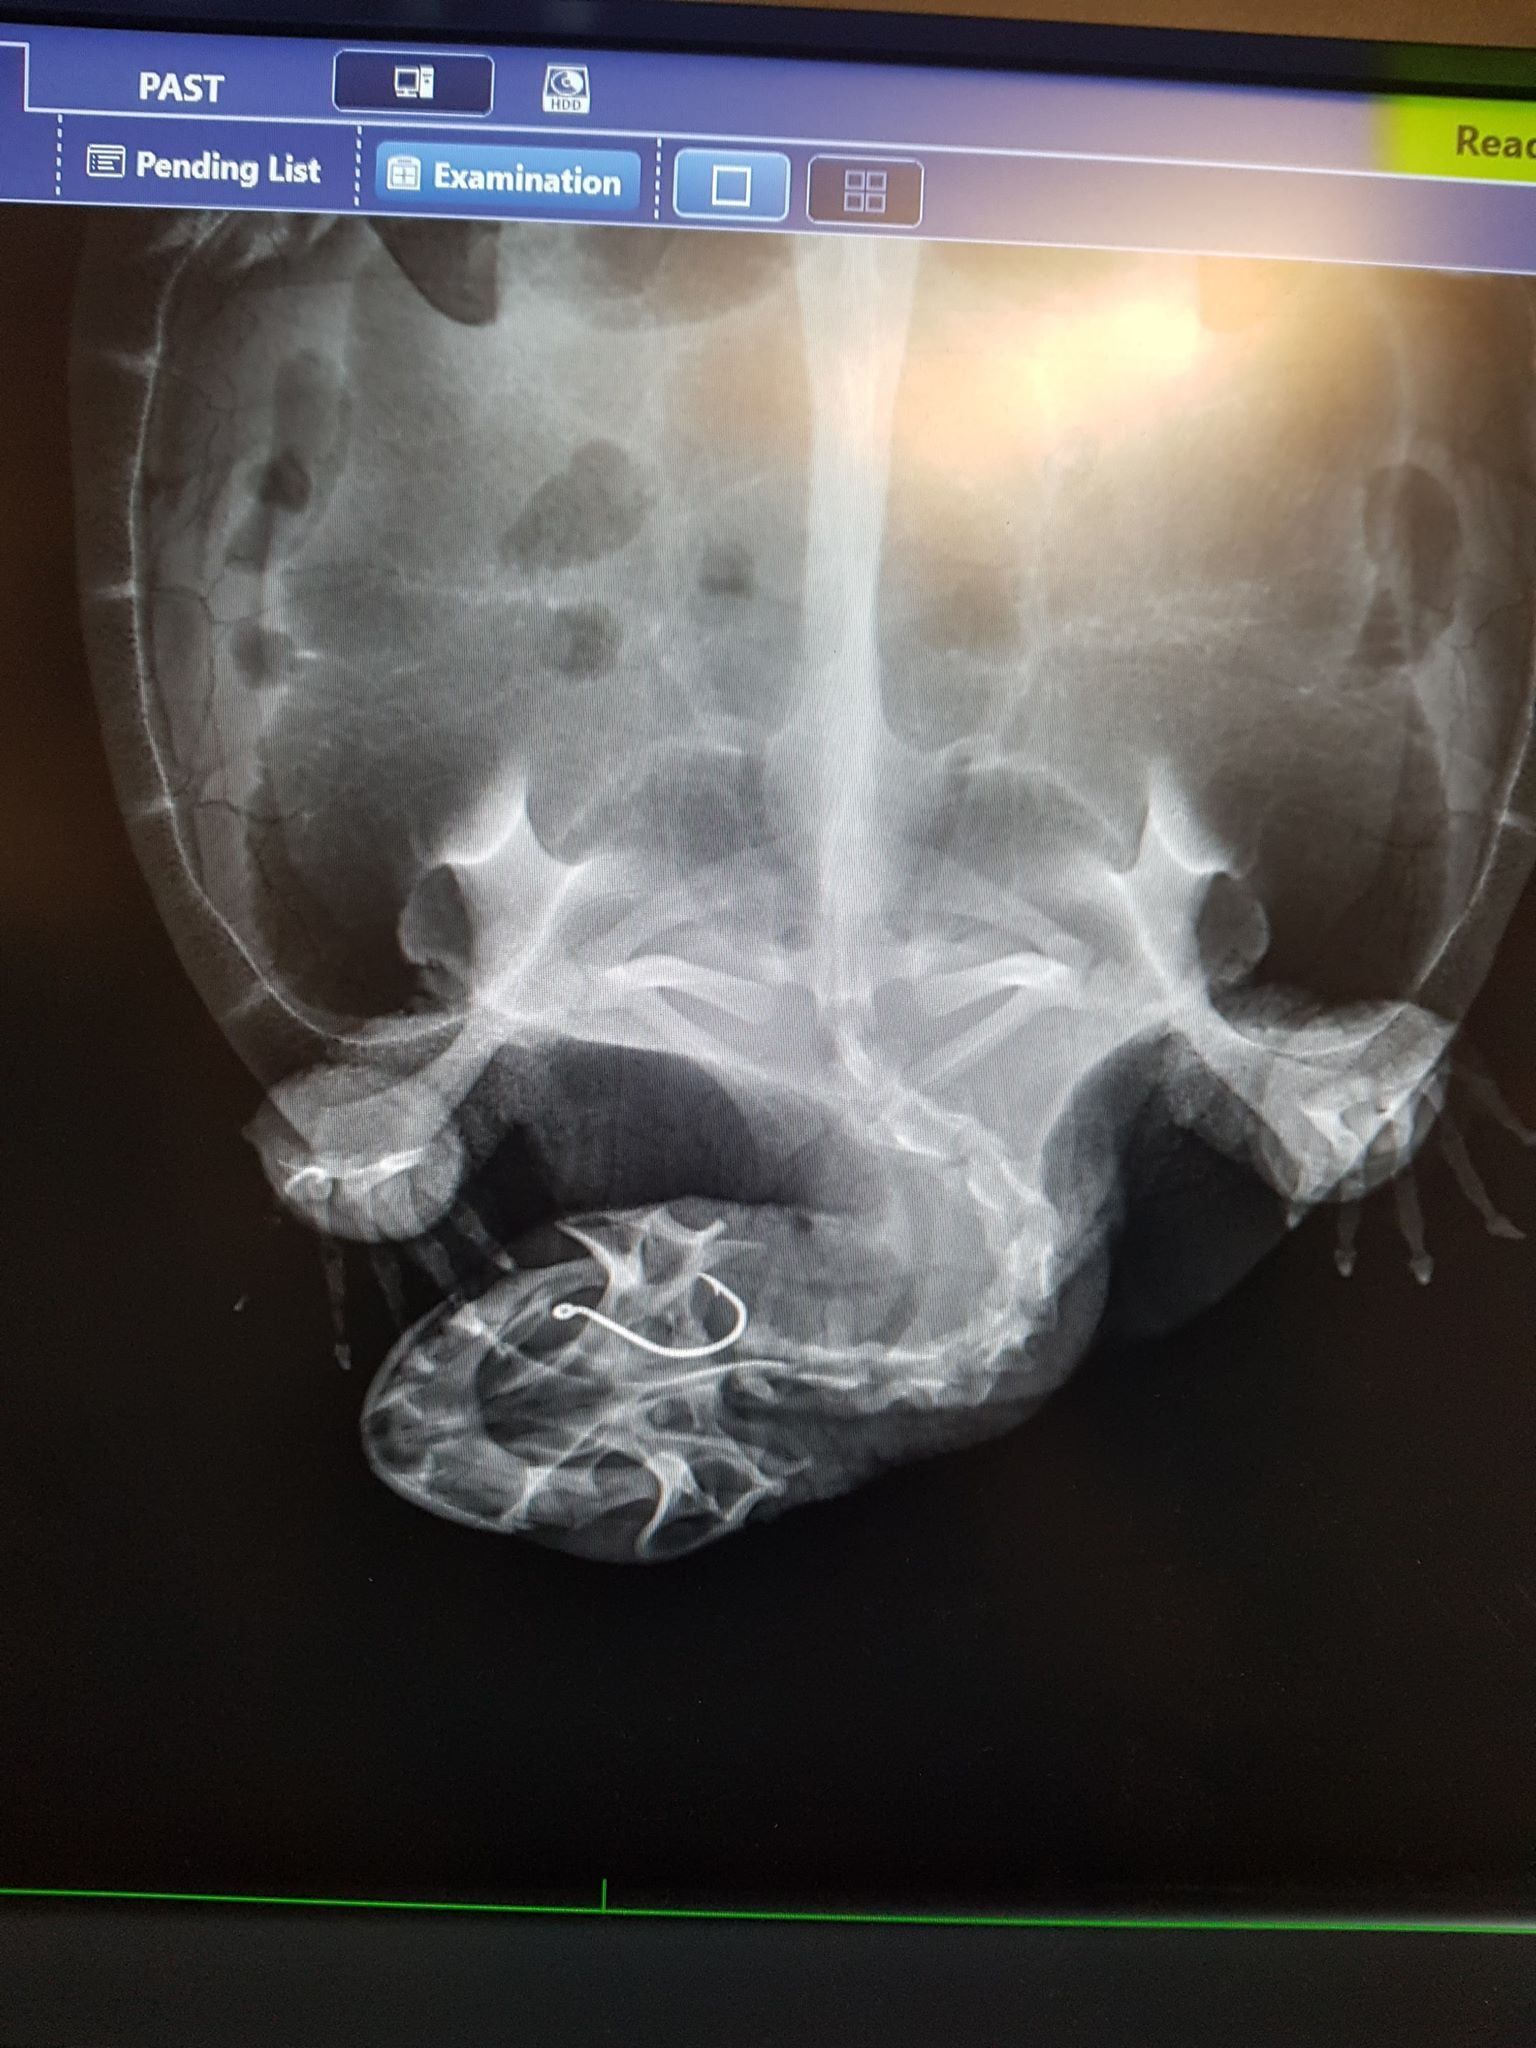

Digital X-rays & Internal Imaging

Diagnostic imaging plays a critical role in veterinary medicine because it allows clinicians to observe internal body structures without invasive procedures.

Digital X-ray technology is used to examine bones, joints, organs and soft tissues. This technology is particularly useful for diagnosing fractures, arthritis, lung conditions and abdominal abnormalities.

Radiographic imaging assists veterinarians in developing accurate treatment plans and determining whether surgery or medical therapy is the most appropriate option.